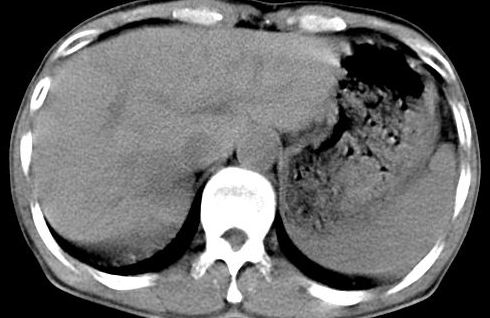

病人资料:男,50岁,上腹部隐痛,消瘦乏力,有乙肝病史二十余年,b超提示肝内内占位。

由于是基层医院,机器速度跟不上,增强效果差,请各位老师也看看!

肝右叶后下内侧段占位:肝癌可能性大

肝右叶后段低密度灶,增强受机器限制,特点不明显,无等密度充填及周围强化,结合病人乙肝史20年,首先考虑肝癌。

肝右后叶占位,增强时期没抓好,特点不明显,结合病史首先考虑原发性肝癌

依据病史,及肝脏占位,应考虑原发性肝癌

考虑肝右叶后下内侧段占位:肝癌可能性大。增强效果很不理想。